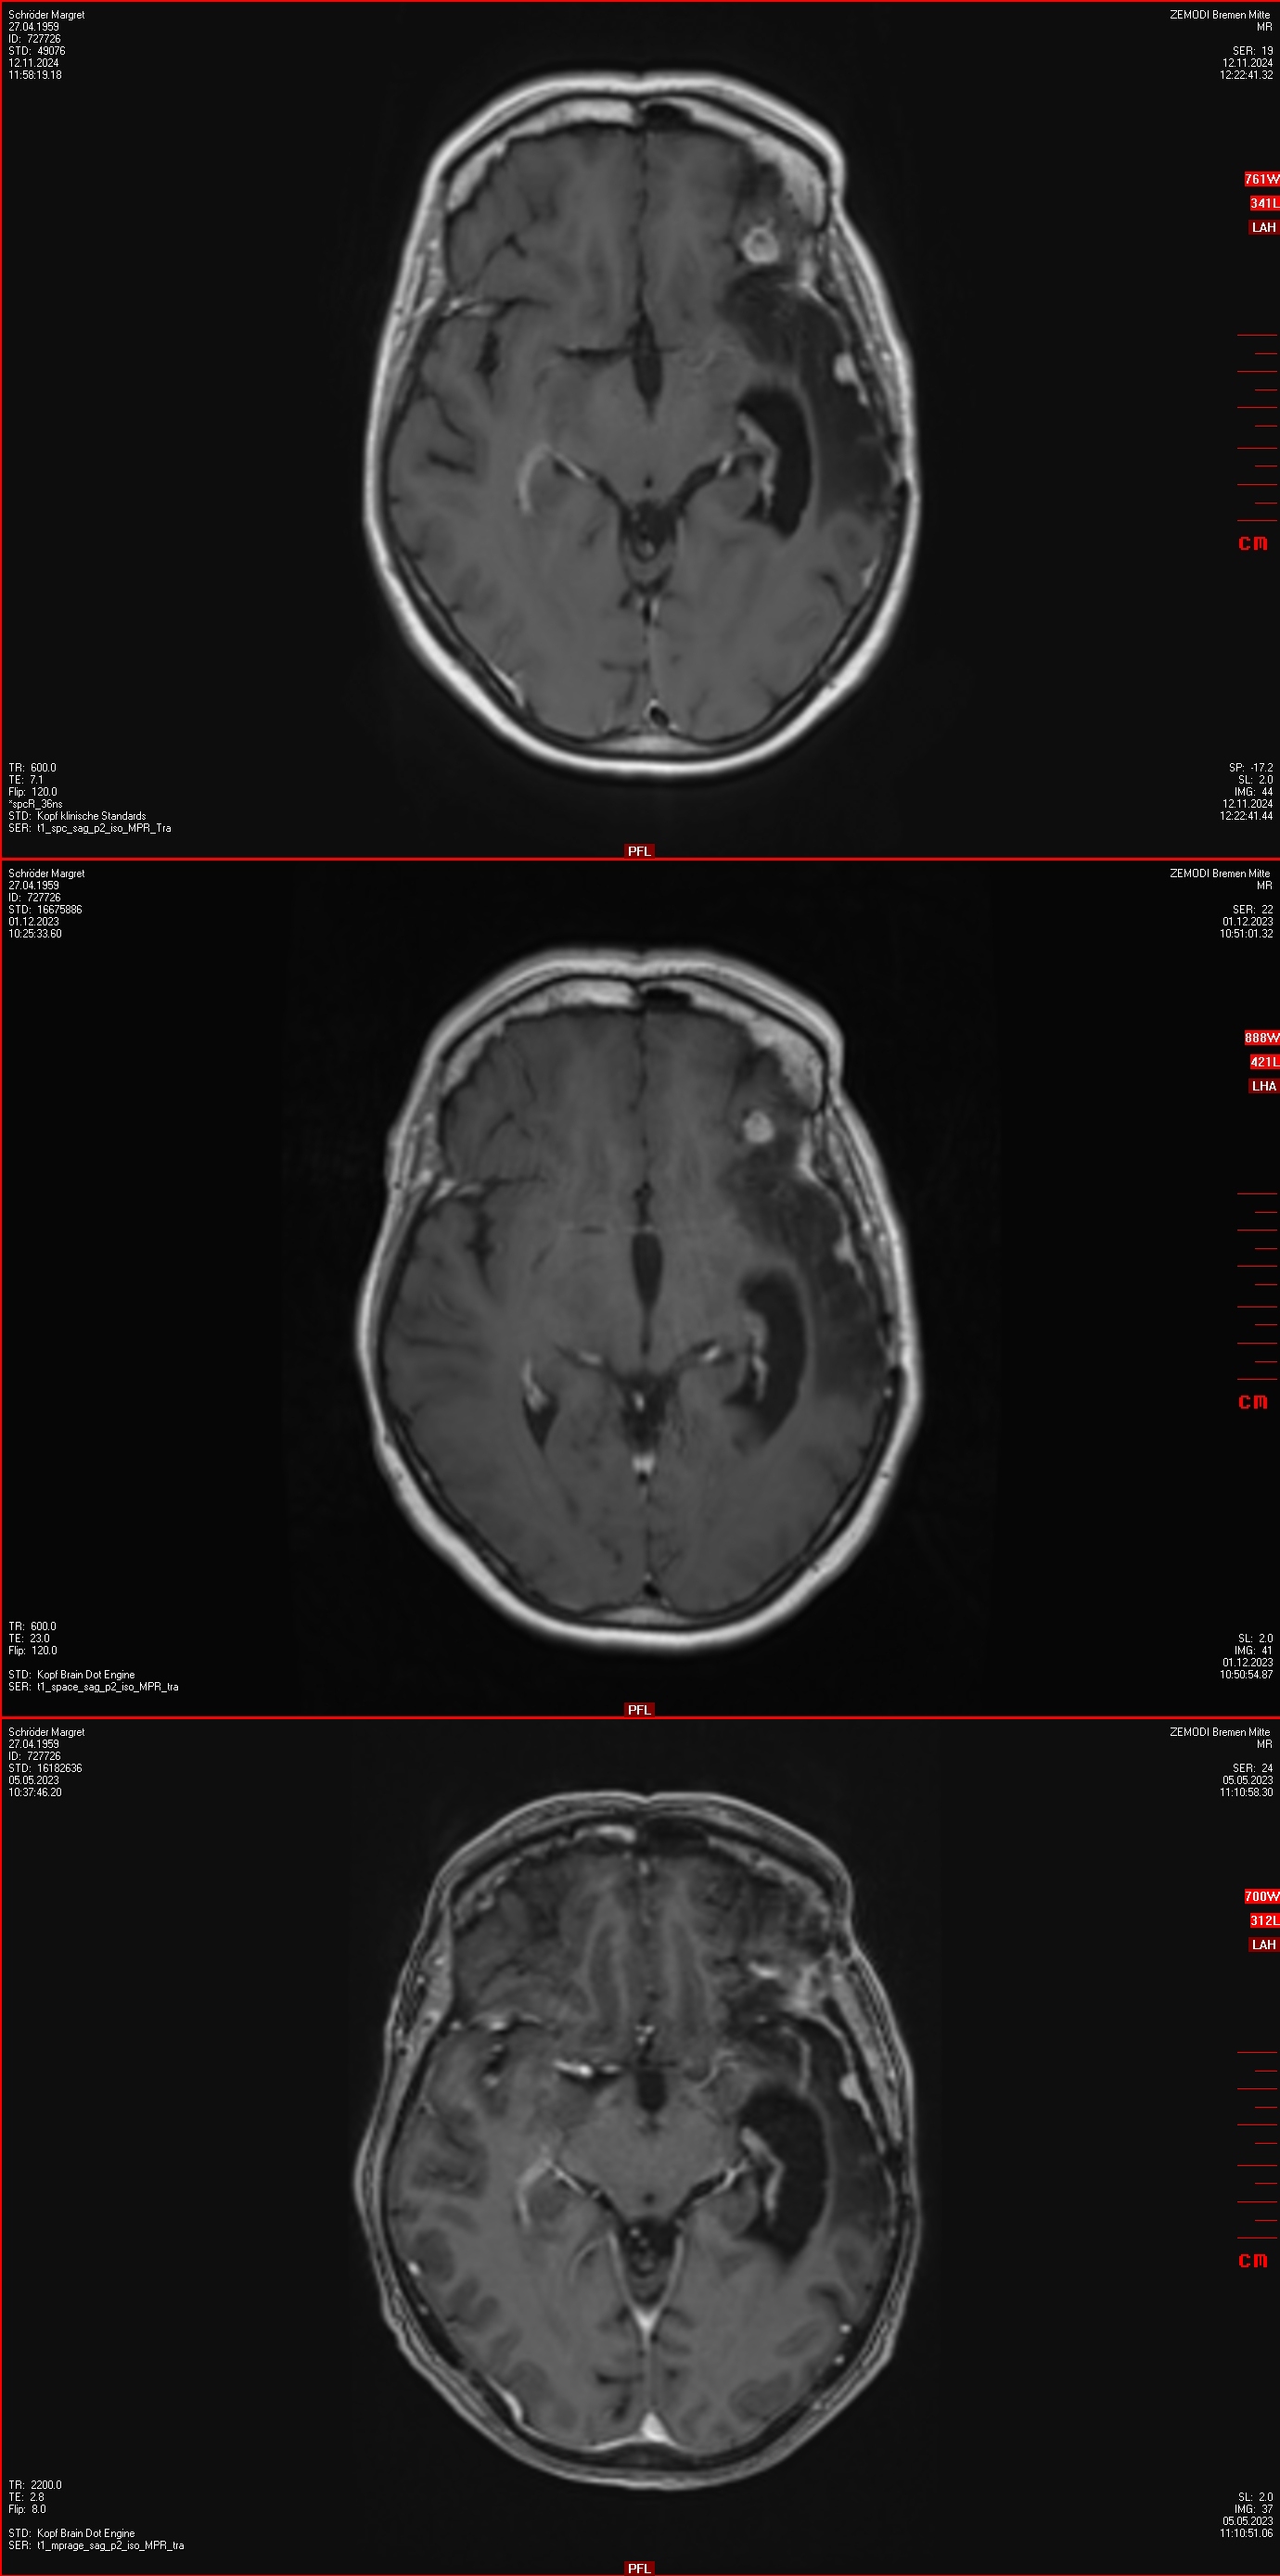

12.11.2024: MRT

• unverändert zur Gamma Knife Behandlungssituation 2021 das kleine links temporale Konvexitätsmeningeom

• Ein progredientes links frontoorbitalis Meningeom (10 mm)

• Ein progredientes Meningeom links frontobasal en-Plaque wachsend mit Raumforderung am linken N.opticus mit Durchmesser 36x13x6mm

• Ein kleines Meningeom links temporamedial am Tentorium (9 mm),

• Ein weiteres sehr kleines links temporales Konvexitätsmeningeom (8 mm),

• Ein progredientes Meningeom links temporaparietaler Übergang (19 x 9 mm)

04.12.2024: OP

• erneute Operation in Bremen: Resektion des größeren linksfrontobasalen Meningeoms sowie des Meningeoms links frontoorbital und und des 2021 im Gamma Knife behandelten Konvexitätsmeningeom

• Histologie : Meningeoms WHO Grad 3 (C228T Mutation im TERT Promotor)

05.12.2024: MRT postoperativ

• komplette Resektion des links frontobasalen Meningeoms, des links frontoorbitalen Meningeoms sowie des  im Jahr 2021 im Gamma Knife behandelten Meningeoms. Die weiteren oben beschriebenen Meningeoms sind unverändert.